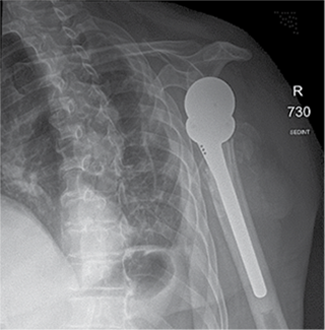

A 58-year-old patient was admitted to the Emergency Department of level I Trauma Center in August 2022 due to polytrauma sustained in a car accident. On arrival, the patient’s condition was severe, with decreased consciousness (GCS score of 12), unstable hemodynamic, subcompensated peripheral circulation, blood pressure of 62/32, and heart rate of 78 beats per minute. There was reduced breathing on the left side with a respiratory rate of 18 breaths per minute and an oxygen saturation (SpO2) of 85.0%. Palpation revealed pain in the left posterior chest. X-rays and CT scans were performed, which revealed a traumatic hemothorax on the left side, humeral head within the pleural cavity, three rib fractures, lung contusion, and hematoma.

Figure 1. First X-ray and computer tomography upon admission (with humeral head shown)